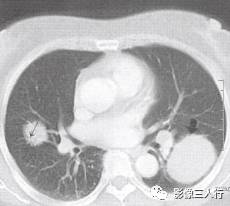

胸部CT图像显示,在含气少的致密肺的背景上见到含气的支气管,表现为两种形态: ①在大片肺实变病灶内的细条状空气密度影;②直径Imm的小泡状空气密度影,连续的几 个层面都能出现(图2、图3)。该征象表明:①近侧气道通畅;②肺泡内的空气经吸收(肺不张)或取代(肺炎、肺癌),或两者综合而消失。通畅含气的支气管在肺泡实变高 密度区内表现为管腔内低密度充气轮廓。